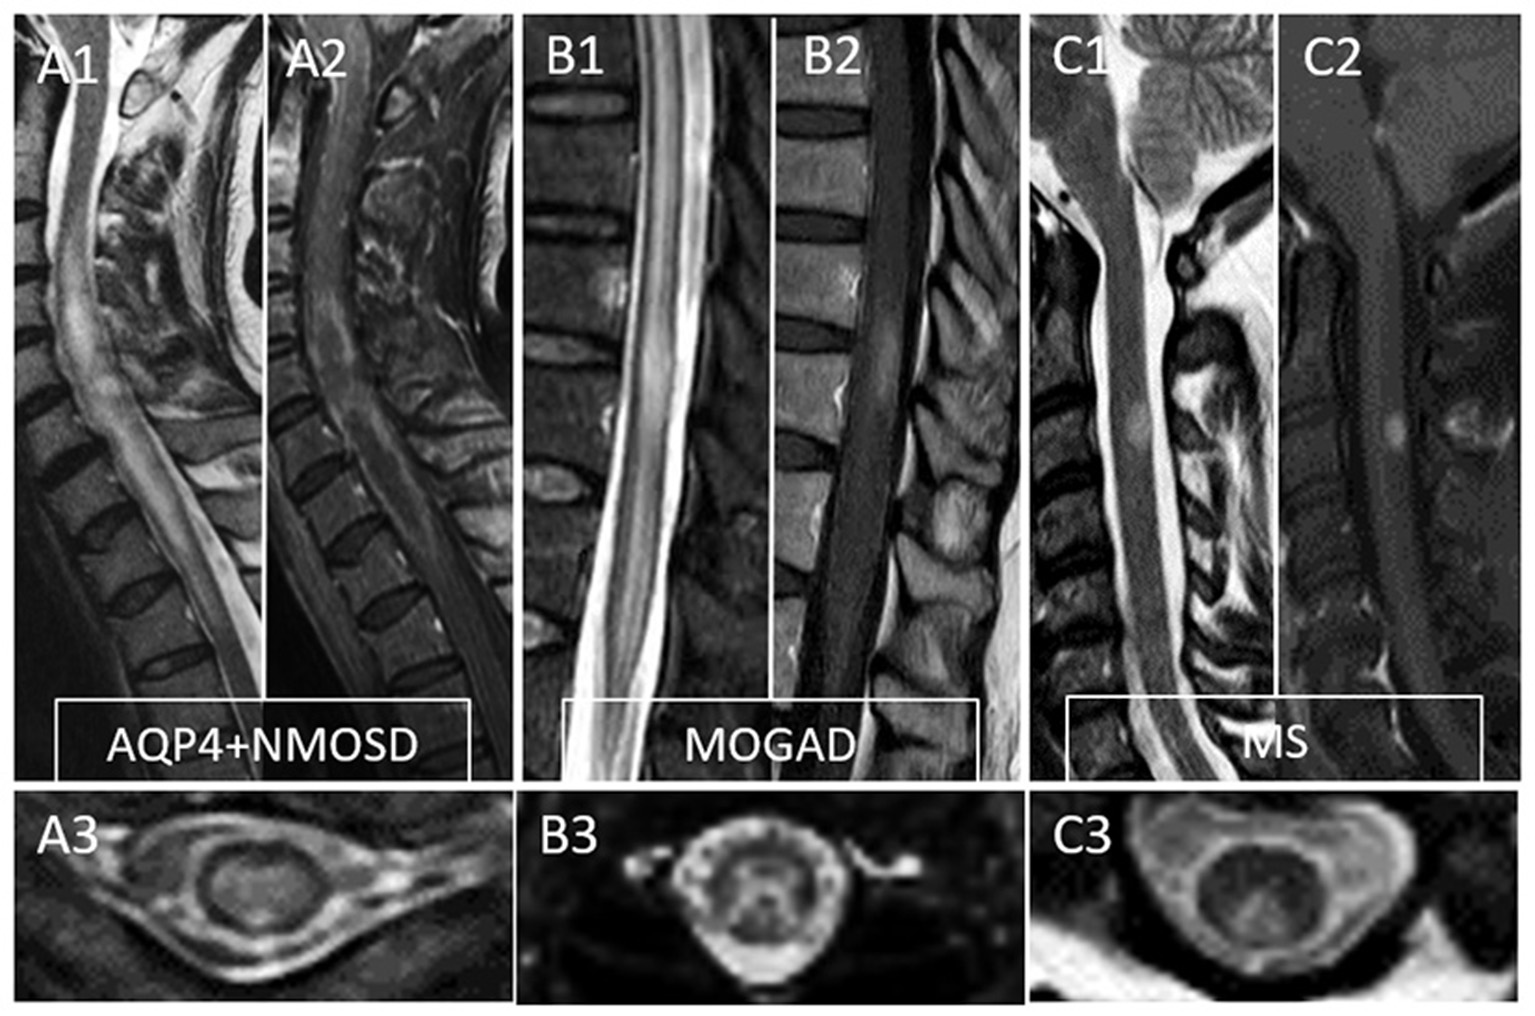

MRI provides essential clues for the differential diagnosis of inflammatory myelopathies, and by virtue of being readily available before the results of antibody testing, it is key in guiding the first treatment decisions. Figure 1 schematically shows the typical location and gadolinium enhancement patterns of different demyelinating lesions on spinal cord MRI, and representative MRI images are shown in Figure 2.

Figure 2

Typical MRI findings in patients with myelitis associated with AQP4-IgG-positive neuromyelitis optica spectrum disorder (AQP4+NMOSD), MOG-IgG associated disease (MOGAD), and multiple sclerosis (MS). A typical longitudinally extensive T2-lesion affecting the cervical spinal cord in a patient with AQP4+NMOSD is evident on sagittal images (A1), with peripheral enhancement after gadolinium administration—“elongated ring” enhancement (A2). Axially, the T2 lesion involves the majority of the spinal cord (A3). In patients with MOGAD myelitis, involvement of the conus medullaris by the longitudinally extensive T2 lesions (B1) is significantly more common compared to NMOSD, with accompanying patchy or nonspecific enhancement in about half of cases (B2). On axial T2 images, a predominant involvement of the central gray matter is common forming a H-sign (B3). Lastly, MS myelitis T2 lesions are typically short on sagittal images (C1) and peripherally located along the dorsal (C3) or lateral columns axially. After gadolinium administration, lesion enhancement can be nodular (C2) or ring-like.